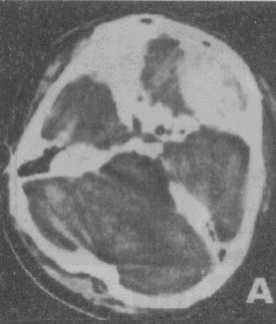

男性,42岁。被汽车撞伤1小时,昏迷状态。急诊CT检查图像如图所示.诊断最可能是

A.脑实质出血

B.脑挫裂伤

C.硬膜下血肿

D.硬膜外血肿

E.蛛网膜下隙出血

[单选题]男性,42岁。被汽车撞伤1小时,昏迷状态。急诊CT检查图像如图所示.诊断最可能是A.脑实质出血B.脑挫裂伤C.硬膜下血肿D.硬膜外血肿E.蛛网膜下隙出

[单选题]男性,42岁。被汽车撞伤1小时,昏迷状态。急诊CT检查图像如图所示.诊断最可能是()A . 脑实质出血B . 脑挫裂伤C . 硬膜下血肿D . 硬膜外血肿E . 蛛网膜下隙出血